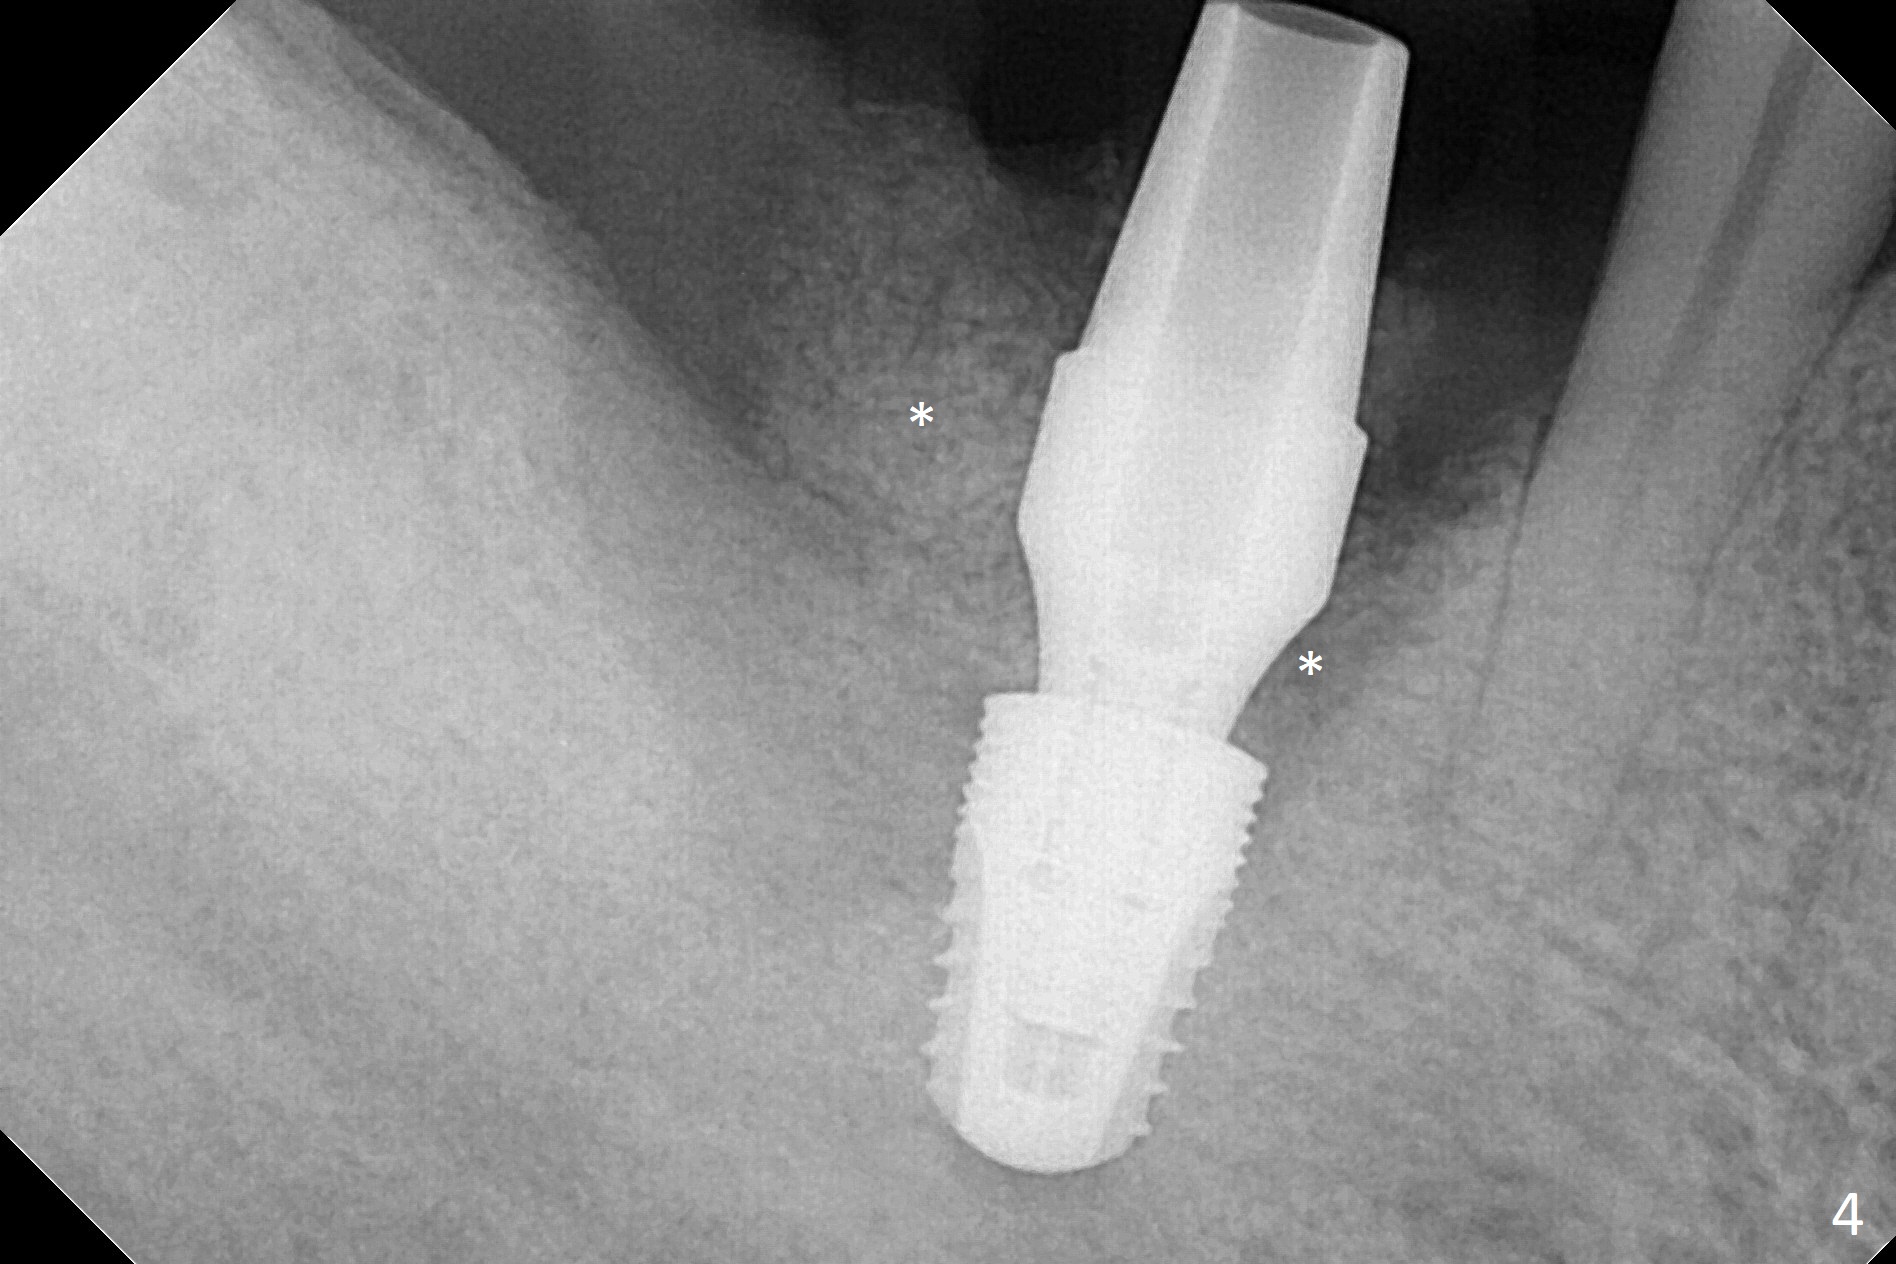

After extraction of the tooth #30, hemorrhage is excessive. With incision and buccal flap elevation, it is easy to remove residual granulation tissue and see the bony defect. With gauze pressure, hemostasis is manageable. Osteotomy is established in the mesial socket, i.e., mesial slope (Fig.1 yellow dashed line) with 2 mm initial drill from DIO Sinus Master Kit with 6 mm stop. After use of 3.8 and 3.6 mm round burs from the Master Kit for 6 mm, 4.1-5x8 mm drills from SM Kit are used with 50 RPM to control depth until the patient feels light pain with infiltration anesthesia. A 5.3 mm tap drill is inserted with 50 Ncm (Fig.2). A 5.3x8 mm SM implant is placed with >55 Ncm with clearance from the Inferior Alveolar Canal (Fig.3 red dashed line) with tightening a 5.8x7(6) mm abutment. The implant is subcrestal mesiolingually, equicrestal buccally and supracrestal distally (Fig.3 thread exposure distally between arrows). With Osteogen plug placed in the distal socket, allograft is placed around the implant and abutment (Fig.4 *). Periodontal dressing is applied following buccal placement of Collagen Dressing and suturing. The gingiva around the abutment is healthy 3.5 months postop; new bone appears to form distocoronal to the implant (Fig.5,6 *).